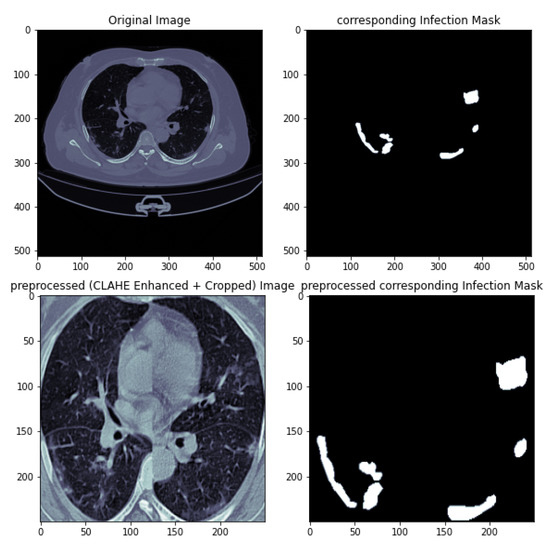

3.4. Data Preprocessing

| Original CT Scan | Lung Mask | Infection Mask | Lung and Infection Masks |

|---|---|---|---|

![]() | ![]() | ![]() | ![]() |